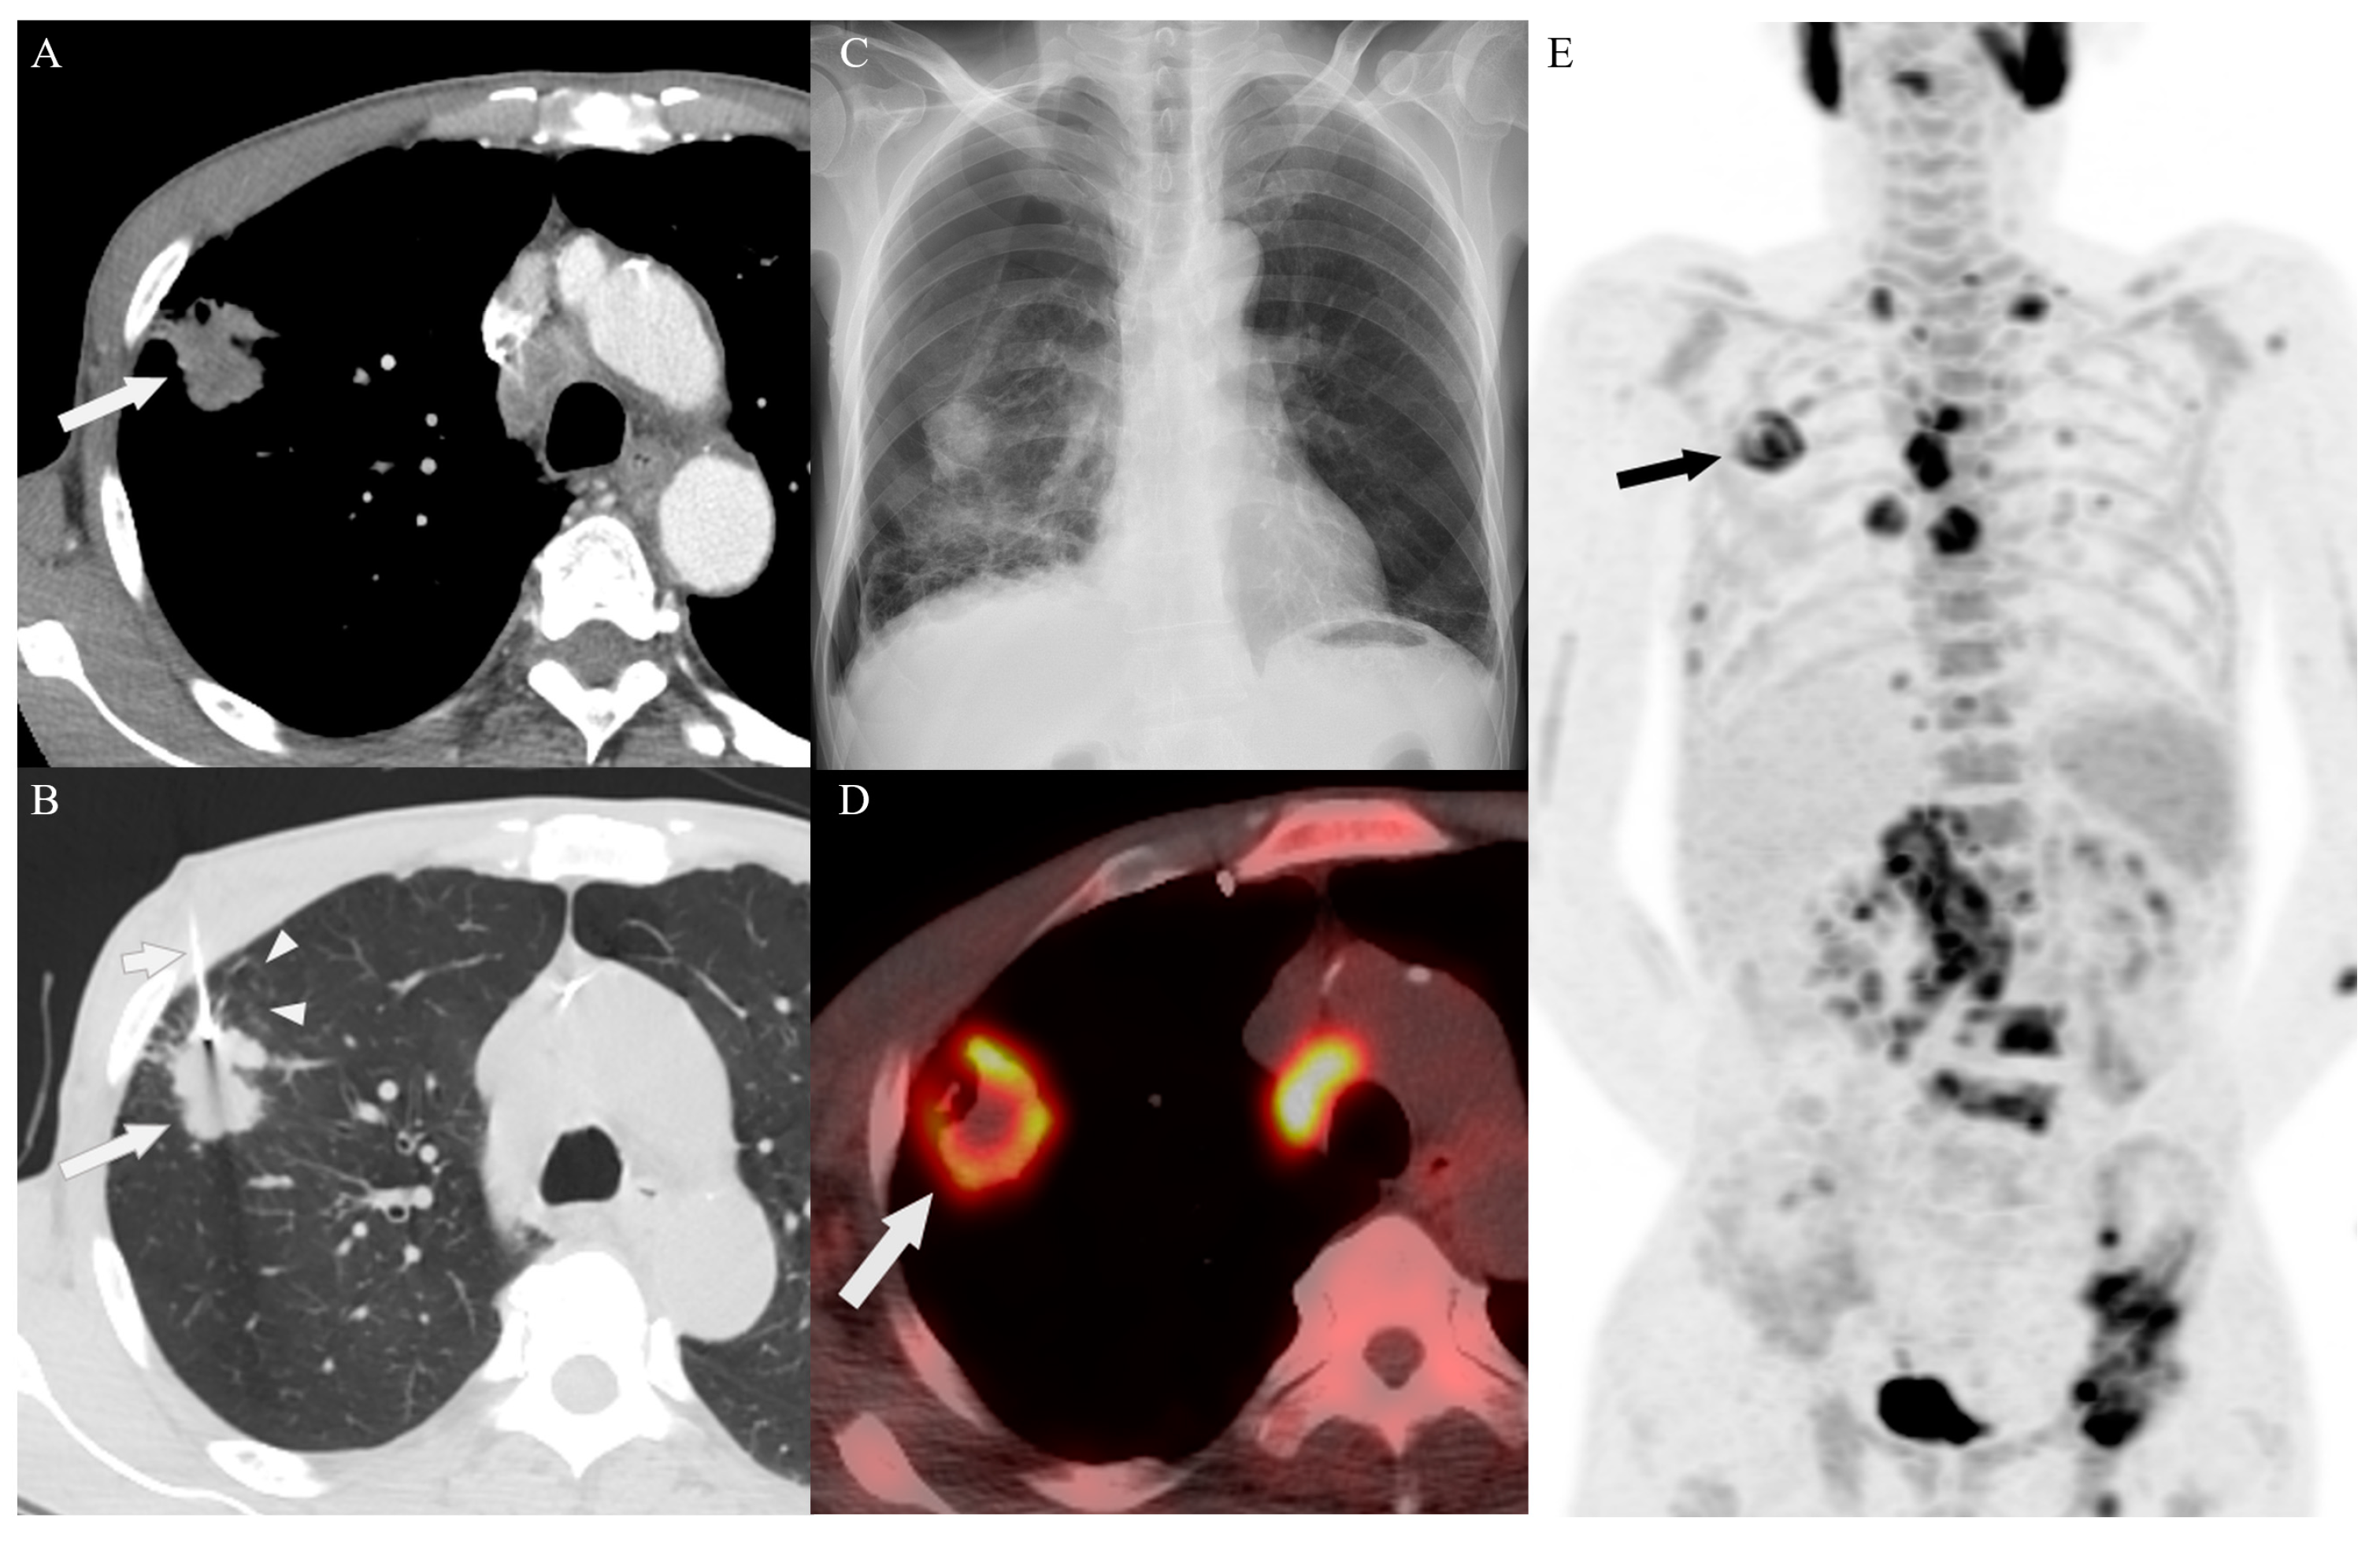

3.2. Biopsy Characteristics and Outcomes

3.4. Target Site Selection, Complications, and Diagnostic Yield According to PET/CT Timing